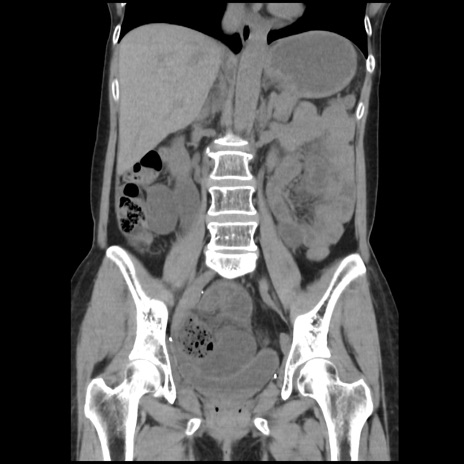

横断像

矢状断像